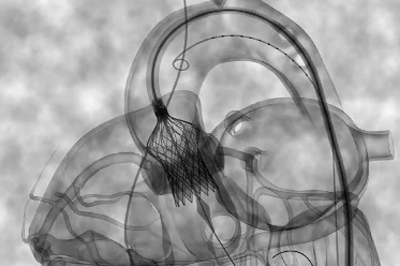

Ученые исследовали 802 пациента высокого риска с тяжелой степенью аортального стеноза, перенесших транскатетерное протезирование аортального клапана.

В открытом исследовании 3 фазы, проводимом в 31 регионе, пациенты были рандомизированы в соотношении 1:1 на применение бивалирудина (болюс 0,75 мг / кг + вливание 1,75 или 1,4 или 1 мг / кг / час) или нефракционированного гепарина (рекомендуемое АЧТВ ≥ 250). Дозирование гепарина и использование протамина было оставлено на усмотрение лечащего врача. Комбинированная основная конечная точка включила массивные кровотечения в течение 48 часов после протезирования или при выписке из больницы и неблагоприятные события (смерть, ИМ, инсульт и кровотечение) в течение 30 дней.

Процедурный успех наблюдался практически у всех пациентов в группе бивалирудина (n = 393; 97,3%) и гепарина (n = 388; 97,5%) руки. Тяжелые кровотечения (BARC ≥ 3b) в течение 48 часов после протезирования или при возникновении первичной конечной точки наблюдались у 28 пациентов (6,9%) в группе бивалирудина и у 36 пациентов (9%) в группе гепарина (ОР = 0,77; 95% ДИ 0.48-1.23). Вторая комбинированная основная конечная точка, чистые неблагоприятные события в течение 30 дней произошли у 58 больных (14,4%) в группе бивалирудина и у 64 пациентов (16,1%) в группе, получавшей гепарин (ОР = 0,89; 95% ДИ 0,64-1,24). Смертность в течение 48 часов составила 1,5% (n = 6) в группе бивалирудина и 1,8% (n = 7) в группе, получавшей гепарин (ОР = 0,85; 95% ДИ 0,29-2,49).

"Массивные кровотечения и неблагоприятные сердечно-сосудистые события были ниже, чем ожидалось, в обеих группах. Использование бивалирудина во время процедуры не существенно снизило риск возникновения тяжелых кровотечений в течение 48 часов или неблагоприятных кардиоваскулярных событий в течение 30 дней по сравнению с гепарином. Бивалирудин может быть альтернативным антикоагулянтом у пациентов, которым планируется транскатетерное протезирование аортального клапан и не может быть назначен гепарин.